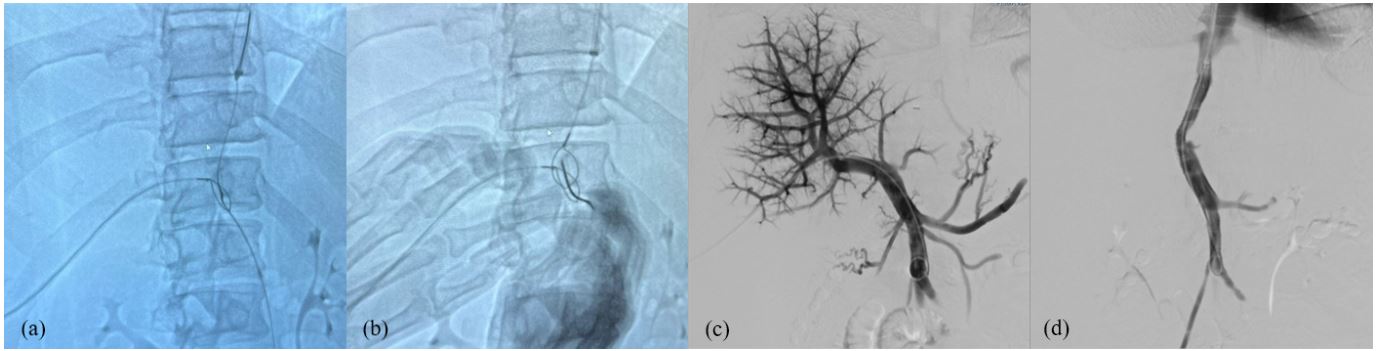

Oral anticoagulation with vitamin K antagonists, cyto-reductive therapy with low-dose hydroxyurea and diuretics (either loop diuretics and k+ sparing drugs) were initiated. Good short and long-term prognosis was estimated by calculating classical risk scores (Rotterdam BCS index 1.0, Clichy prognostic index 4). Since blood biochemistry did not improve over time and the patient required paracentesis for symptomatic tense ascites despite optimal medical therapy (Child-Pugh B9-C10), a work-up evaluation for TransJugular Intra-Hepatic Porto-Systemic shunt (TIPS) placement was done. Significant cardiac systo-diastolic dysfunction as well as pulmonary hypertension were excluded performing a trans-thoracic echocardiography. After a detailed multidisciplinary discussion with the interventional radiologist we concluded that the classical direct trans-jugular and trans-caval approaches for stent placement were not feasible because of an unexpectedly hard fibrotic wall of the intra-hepatic IVC. For this reason, 2 metal guides, were previously placed inside the IVC (via trans-jugular route) and the right portal branch (through a trans-hepatic access) and then connected by another percutaneously-inserted needle (Gun-Sight technique) to create the final 8 millimeter-dilated and 6 cm-long TTIPS (Trans-Jugular Trans-Caval Intra-Hepatic Porto-Systemic shunt) implantation (Figure 1). At the end of the procedure, a contrast medium-based fluoroscopy confirmed both the patency and the correct functioning of the shunt, with nearly no portal flow through hepatic parenchyma. A CT scan after TTIPS placement showed a well-placed stent between IVC and portal bifurcation without any procedure-related complications. After 1 month, a significant clinical and biochemical amelioration was noticed: the ascites disappeared and blood tests (transaminases and bilirubin) were normalized. A focused Color-Doppler US showed a patent stent with normal-velocity hepatofugal blood flow (peak medium velocity from 90 cm/s in proximal/medial tract to 140 cm/s in distal part of the TTIPS, see Figure 2) and a significant decrease in hepatic and splenic stiffness and arterial resistance indexes (for liver: 25 to 12 kPa and RI 0.75 to 0.52; for spleen 35 to 25 kPa and RI 0.73 to 0.48), suggesting effective splanchnic decongestion and amelioration of portal hypertension (Figure 2). The patient discontinued diuretic therapy and a direct oral anticoagulant with a full dosage of apixaban was started; since the risk of thrombosis and TIPS dysfunction, the patient is undergoing a biochemical and US follow-up every three months; he is still fine.

Figure 2: Hepatic hemodynamic after T-TIPS. (a) Right branch of portal vein with hepatofugal flow after TTIPS entrance; (b,c,d). show patent TTIPS with normal flow velocity and slight flow turbolence in the distal part of the shunt; distal end of the TTIPS directly enter in IVC in (e,f); very low arterial Resistance Index (RI) of both liver (g) and spleen (h) after TTIPS, demonstrating highly effective decongestion of the splanchnic district.